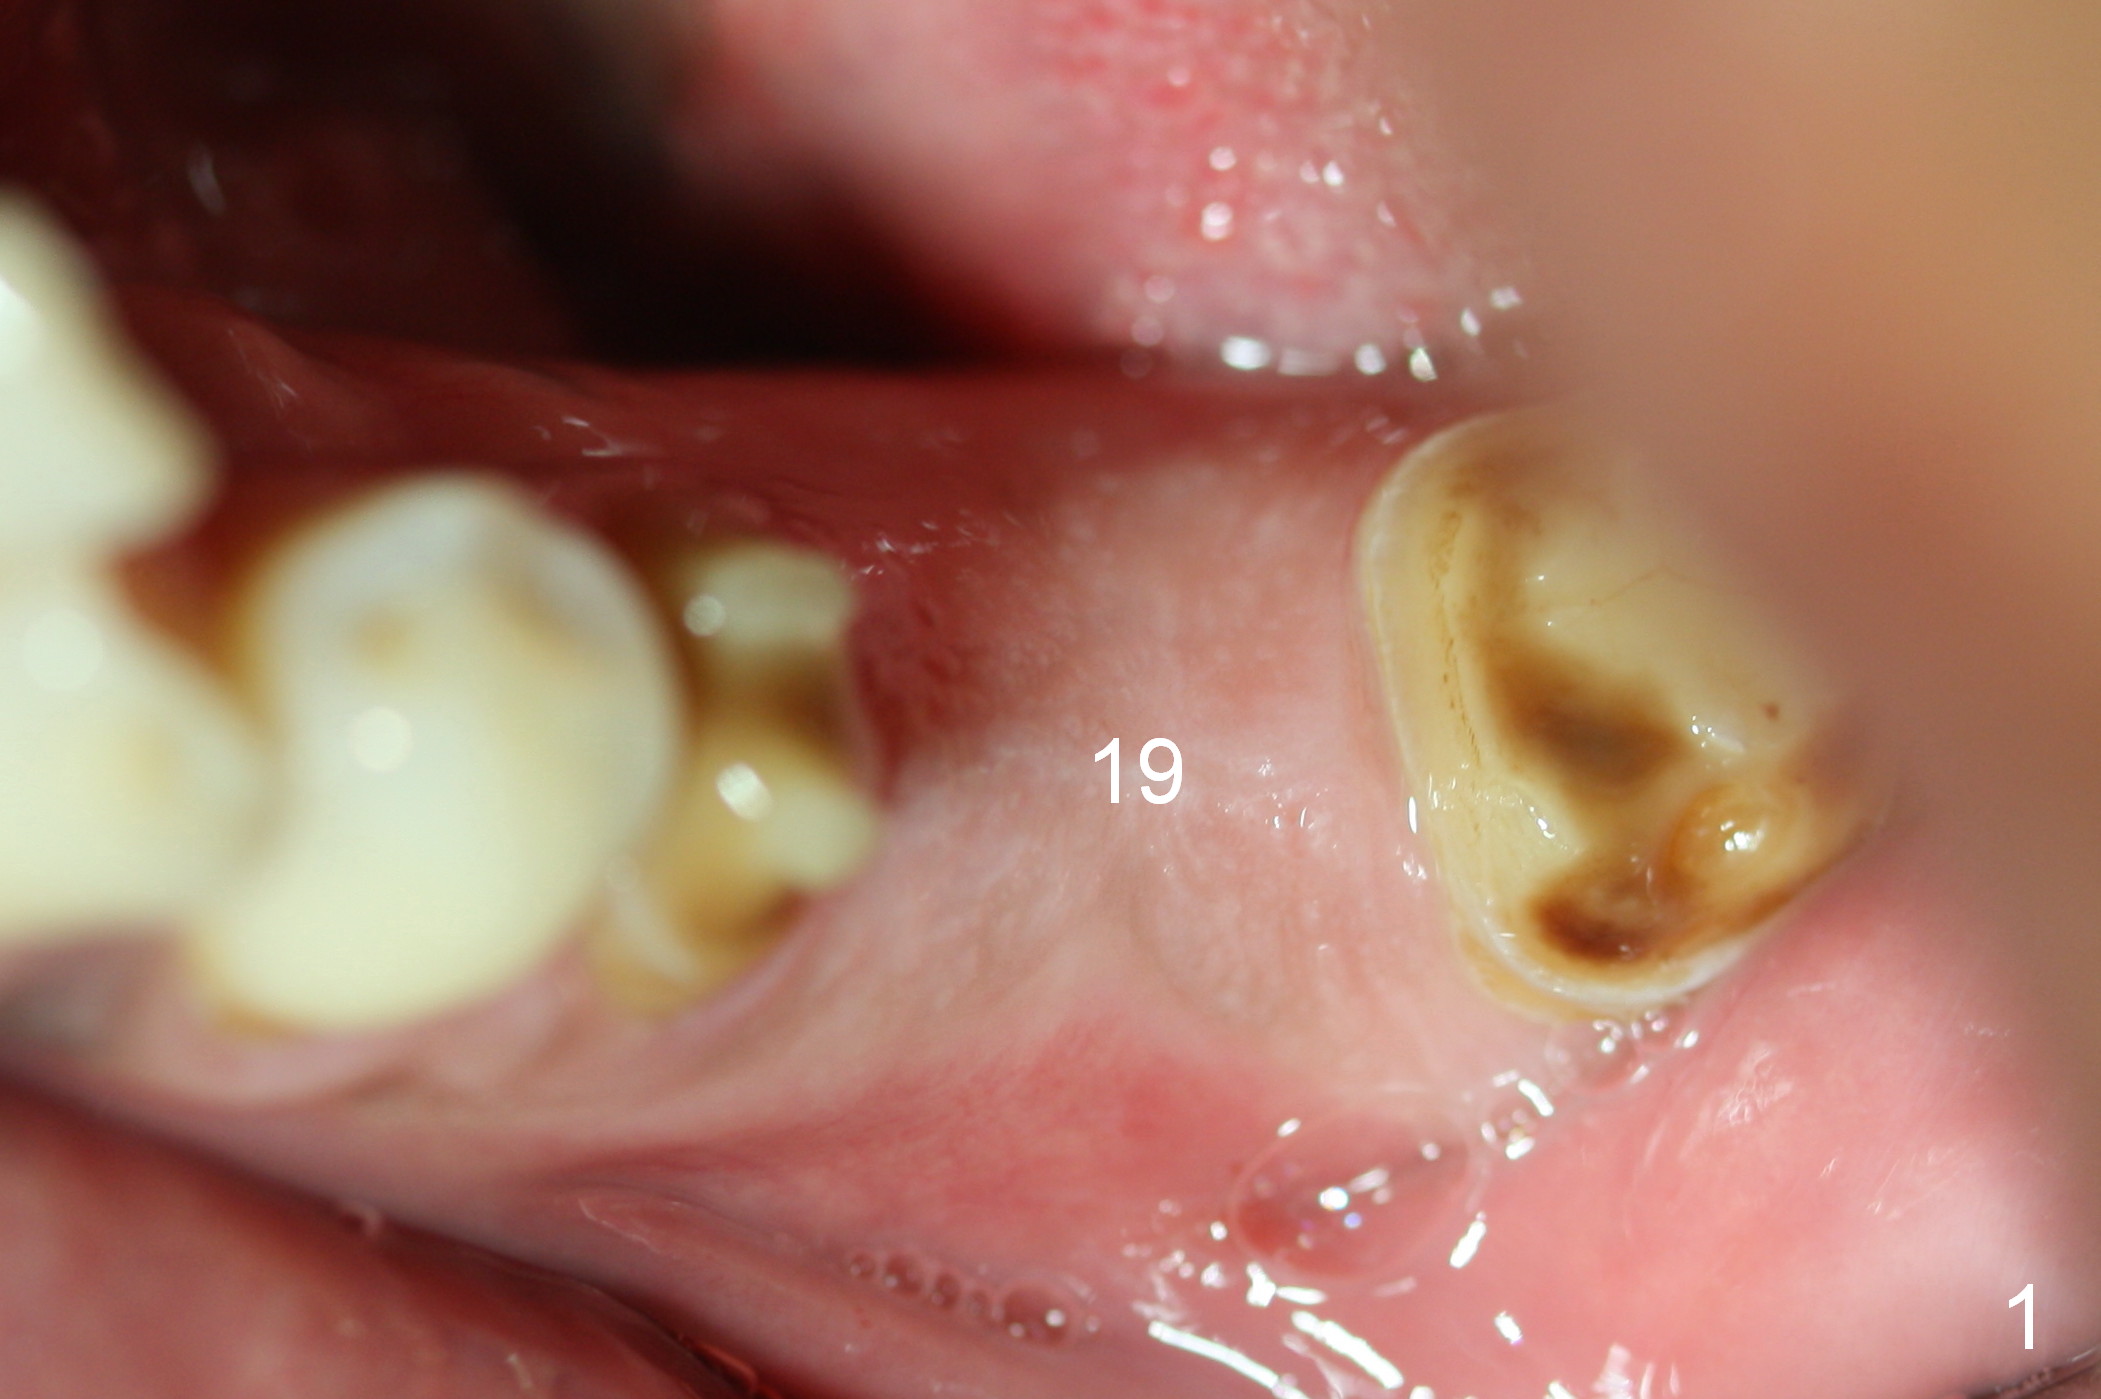

When the patient returns for implant placement, he is pleased to let us know that he has stopped smoking for a week. The edentulous ridge at #19 looks wide (Fig.1). The tooth #3 is supraerupted, while there is no clearance between the abutments (#18 and 20) and the opposing dentition (Fig.2). After incision, the ridge is confirmed to be wide with the aid of implant positioners. The bone is felt soft during initial osteotomy (Fig.3). Attention is being paid to correcting the trajectory. Under prep is ignored. When a 5.9x10 mm implant is placed, the insertion torque is between 25 and 30 Ncm (Fig.4).